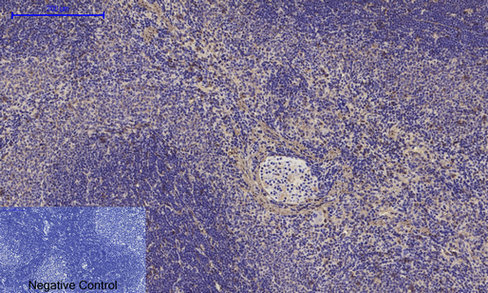

- Submitted by

- St John's Laboratory (provider)

- Main image

- Experimental details

- Immunohistochemical analysis of paraffin-embedded Rat-spleen tissue. 1, Alpha-SMA Polyclonal Antibody was diluted at 1:200 (4°C, overnight). 2, Sodium citrate pH 6.0 was used for antibody retrieval (>98°C, 20min). 3, Secondary antibody was diluted at 1:200 (room tempeRature, 30min). Negative control was used by secondary antibody only.